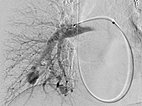

Verschluss der pulmonalen AVM des Oberlappens durch Einbringen von mehreren Platindrahtsprialen (Coils) über den Mikrokatheter unter Schonung der nicht pathologischen Lungenarterien.

Die zuführenden Arterien werden mit mehreren Coils verschlossen. Zur sicheren Verankerung werden Teile der Coils in die arterielle Aufzweigung gelegt (Anker-Technik). Die pulmonale AVM ist verschlossen. Im ehemaligen Aneurysma steht noch etwas Kontrastmittel von einer vorherigen Injektion.